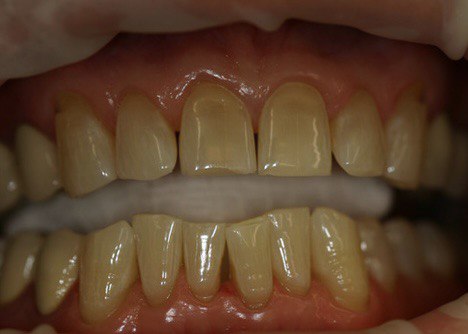

До процедуры цвет зубов А3 по шкале VITA, после процедуры цвет зубов В1 по шкале VITA.

Пациенту рекомендована замена коронок на жевательных зубах, так как они не соответствуют цвету отбеленных зубов.

Результат лечения